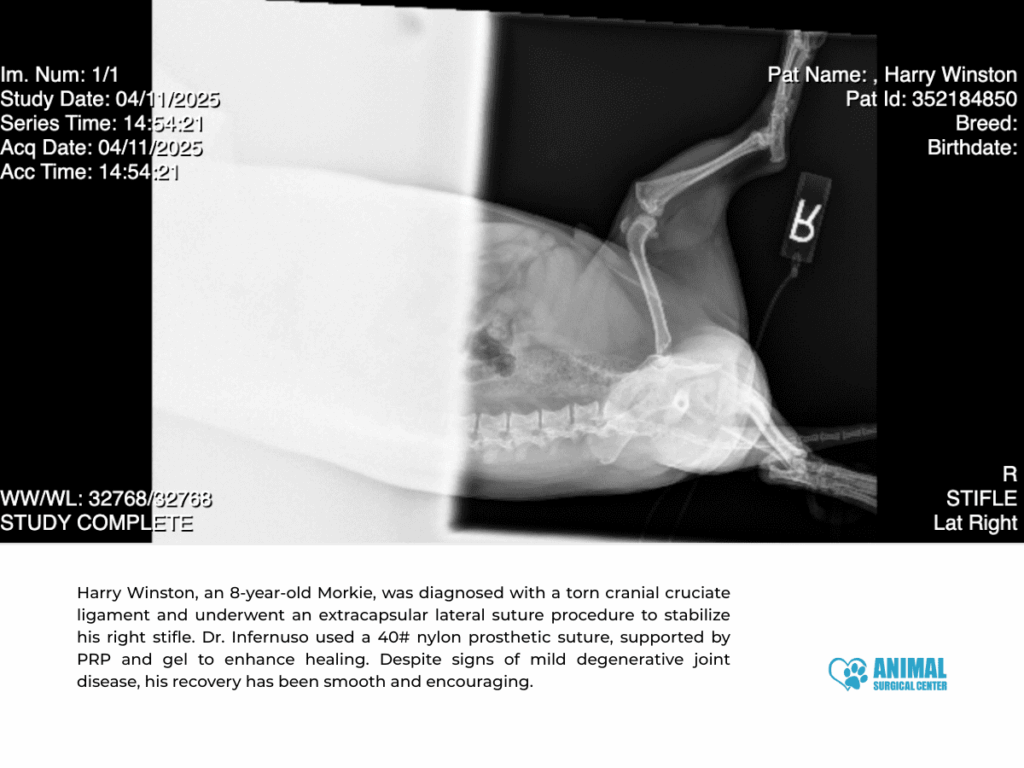

Case Study 2: Harry Winston (Lateral Suture)

- Patient: Harry Winston, 8-year-old Morkie, 6 kg

- Presenting Concern: Limping, suspected ACL tear

- Exam Findings: Positive cranial drawer, mild hip dysplasia, MPL grade 1 on opposite limb

- Surgery Date: April 11, 2025

Procedure: Lateral suture repair was completed using 40# nylon, with supportive PRP and gel. No meniscal damage was found, and joint degeneration was mild to moderate.

Recovery: At his 2-week recheck, Harry Winston was comfortable and eager to be active again. He also completed several sessions of laser therapy to aid recovery.